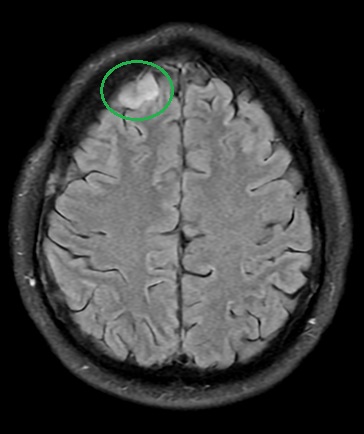

Jak rozpoznać oponiaka w rezonansie magnetycznym?

Podstawowym badaniem jest rezonans magnetyczny (MRI) głowy z kontrastem.

Typowe cechy oponiaka w MRI to:

- guz przylegający do opony twardej,

- silne i zwykle jednorodne wzmocnienie kontrastowe,

- często obecny tzw. „ogon oponowy” („dural tail”), czyli wzmocnienie opony w sąsiedztwie guza.

Co opisuje radiolog?

W opisie badania często pojawiają się:

- „Silne wzmocnienie kontrastowe” – typowe dla oponiaków.

- „Dural tail” – charakterystyczny, choć nie zawsze obecny.

- „Obrzęk mózgu wokół guza” – może odpowiadać za objawy, takie jak bóle głowy czy napady padaczkowe.